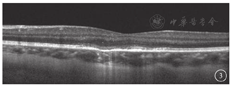

患者女,28岁。因左眼视力下降1周于2015年7月14日至淄博市中心医院眼科就诊。既往身体健康,无吸烟、饮酒史;无猫、狗等宠物接触史。自诉发病前1周出现咳嗽、流涕、发热等流行性感冒样症状;感冒症状好转后左眼出现视力下降。眼部检查:右眼视力0.3,-5.00 DS→1.0;左眼视力0.1,不能矫正。双眼眼前节检查未见明显异常。右眼视盘边界清楚,颜色淡红,血管走形正常,黄斑中心凹反光可见;左眼黄斑区约1 DD大小圆形淡黄色病灶,边界清晰,中央有不规则细点(图1)。FFA检查,左眼早期黄斑区出现不规则强荧光,周围包绕一圈弱荧光,随时间延长荧光增强;晚期黄斑区呈圆盘状强荧光,中心仍有弱荧光(图2)。OCT检查,左眼黄斑区视网膜外核层结构紊乱,外界膜及椭圆体带高低不平,嵌合体区局限性缺失(图3)。OCT血管成像(OCTA)检查,黄斑区脉络膜毛细血管扩张,局部呈强血流信号,未见明确异常血管(图4)。实验室检查,血常规、输血四项、血生化正常。TORCH检测:弓形虫IgM(-)、风疹病毒IgM(-)、巨细胞病毒IgMⅡ(-)、单纯疱疹病毒混合型IgM(-)。结核菌素试验阴性,胸部X线片检查正常。诊断:左眼急性特发性黄斑病变(AIM)。因患者处于哺乳期,未给予干预,随访观察。

对于本病的诊断应根据病史结合眼底表现及影像学检查。本例患者为健康青年女性,双眼近视。有感冒发热病史,单眼视力突然急剧下降,黄斑区视网膜色素改变,FFA表现为透见荧光和遮蔽荧光,典型表现为病灶中心弱荧光,周边环形强荧光"牛眼"样外观[4]。OCT显示RPE及外层视网膜病变,早期RPE水肿,强反射物质堆积,椭圆体带中断、不连续。随着病程的发展,外层结构逐渐修复。OCTA可见脉络膜毛细血管层血流信号增强,未见异常新生血管。患者多模式影像学表现典型,根据以上临床特征AIM诊断明确。本病主要累及外层视网膜及RPE。观察本例患者整个病程OCT,推测急性期视力下降可能与黄斑区视网膜外层结构损伤有关。